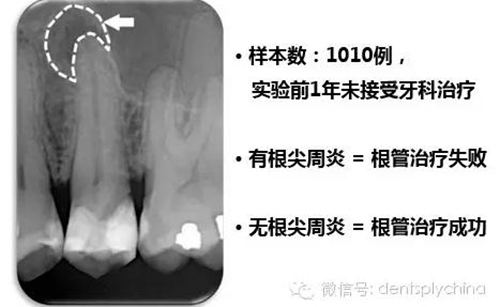

根管治療后牙齒的根尖周狀態(tài)和根管充填和冠部修復(fù)的關(guān)系

成功標(biāo)準(zhǔn): 根尖周健康 = 沒有根尖周炎

根管治療成功率和嚴(yán)密的冠部封閉密切相關(guān)